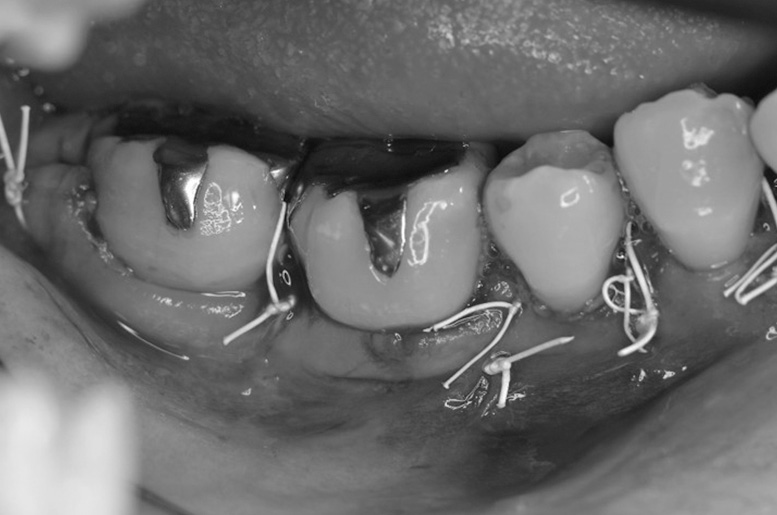

歯周再生療法 精密根管治療 歯周矯正治療 ジルコニアセラミック治療